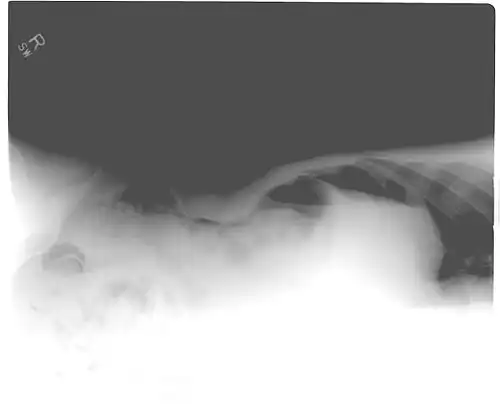

Another pneumoperitoneum on chest X-ray. -

When present, pneumoperitoneum can be seen on projectional radiography, but small amounts are often missed, and CT scan is nowadays regarded as a criterion standard in the assessment of a pneumoperitoneum.[18] CT can visualize quantities as small as 5 cm3 of air or gas.

Signs that can be seen on projectional radiography are shown below: